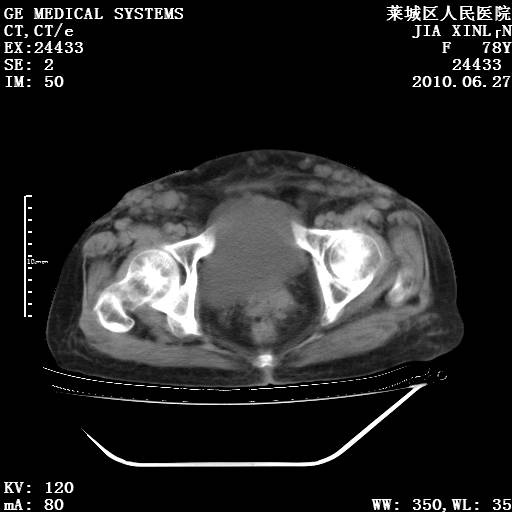

以下是引用胡宇在2010-7-2 19:11:00的发言:[br]神经纤维瘤的特点为:肿块呈多发性、数目不定,少的几个,多的可成百上千难以计数。小的如米粒,大的似拳头,甚至可达十数公斤以上。可松弛地悬挂于皮表,皱褶及松弛可致畸形明显。神经纤维瘤沿神经干的走向生长时呈念珠状,或蚯蚓块状形结节。此外神经纤维瘤皮肤可出现咖啡斑,大小不一,形如雀斑小点状,或大片状,分布与神经纤维瘤肿块的分布无关。肿瘤数目不多的患者,皮肤色素咖啡斑状沉着是纤维神经瘤的重要诊断之一。 本病多发于躯干,有时出现于四肢及面部,患者常合并许多疾病应予重视加以区别。 [br] [br] [br] [br]lyb999说 [br]